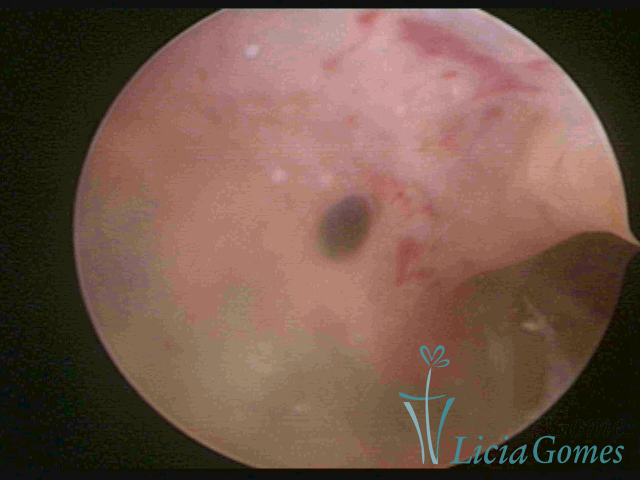

ADENOMIOSE

É a presença de tecido endometrial na camada muscular do útero

A vídeo-histeroscopia permite diagnosticar às lesões próximas às camadas miometriais superficiais, próximo ao endométrio visualizando lesões de coloração violácea, circunscritas, ou acastanhadas com conteúdo achocolatado.